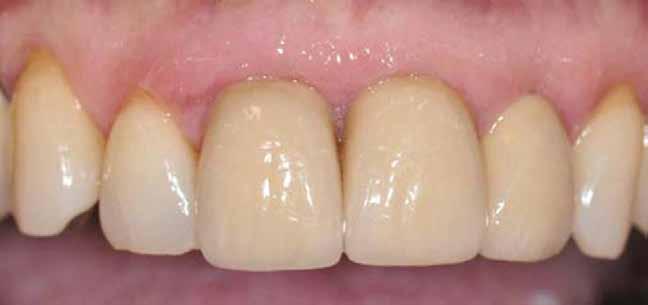

8. a–b. ábra: Végső röntgenfelvétel az implantátum helyzetéről (a) és a szájon belüli végső szituáció az 1. esetről (b).

Végső röntgenfelvétel az implantátum helyzetéről (a) és a szájon belüli végső szituáció a 2. esetről (b).

ábra: Végső röntgenfelvétel az implantátum helyzetéről (a) és a szájon belüli végső szituáció a 3. esetről (b és c).

tottuk (az okklúziós koncepciók alapján az implantációs pótlások nem voltak vezető fogak, és csak könnyű érintkezéseket alakítottunk ki, amelyeket artikulációs papírral ellenőriztünk). A páciensek instrukciókat kaptak a megfelelő szájhigiénére vonatkozóan, összpontosítva a fogköz kefékkel történő tisztítására. Végső kontroll röntgenfelvétel készült. A PEEK felépítmény nem radioopák, így az implantátum és a korona közötti távolság könnyen meghatározható a röntgenfelvételen: a felépítmény megfelelően illeszkedik az implantátumban, ha az implantátum válla és a korona alsó széle közötti rés 0,55 mm a röntgenfelvételen (8–11. ábra)

11. a–b. ábra: Végső röntgenfelvétel az implantátum helyzetéről (a) és a szájon belüli végső szituáció a 4. esetről (b).